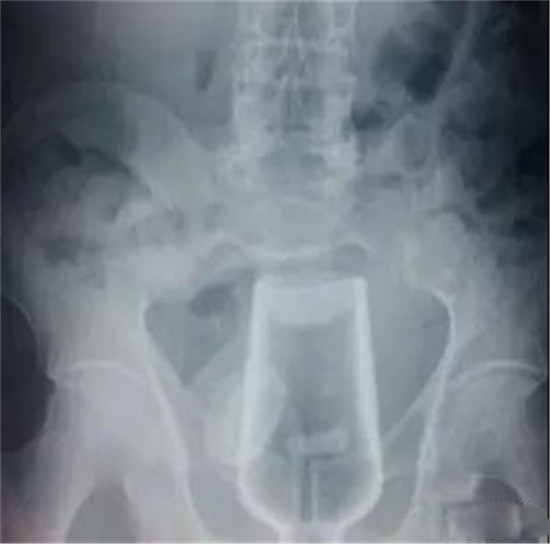

这个是什么瓶子?

这也是一个玻璃瓶。也需要麻醉下取出来。